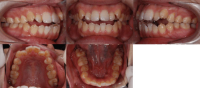

Before

After

| 年齢 | 範囲 | 抜歯有無 | 費用 |

|---|---|---|---|

| 25歳7ヶ月 | 全体矯正 | 有 | 80万円 |